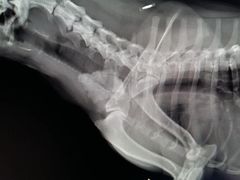

• 爱侣宠医·鹦鹉专科·小型哺乳类·异宠专科(灵石路店)

• -爱侣宠医·鹦鹉专科·小型哺乳类·异宠专科(灵石路店)

I_PRADA | 16-01-06